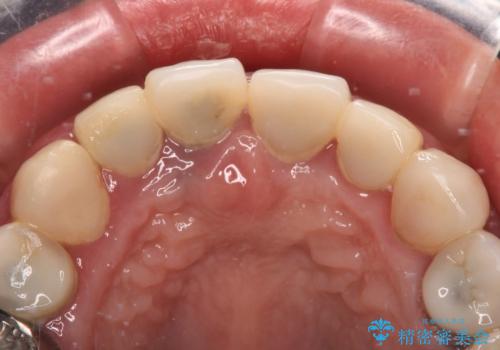

周辺の歯は20年以上前に装着したクラウンで、色合いや形態が気になっているとのことで、オールセラミックブリッジにて補綴治療を行うこととしました。

まずは土台の歯を引っぱり出し、外科処置により歯肉の状態を十分に整えた上で、オールセラミッククラウンにて補綴することとしました。

元々の土台は歯肉の中に埋もれており、歯肉が著しく腫れている状態だったため、歯を引っぱり出すこととしました。引っぱる期間は2ヶ月ほどで済み、その後歯周外科処置を行ったことで、土台周りの歯肉は腫脹のない健全な状態へと改善されました。